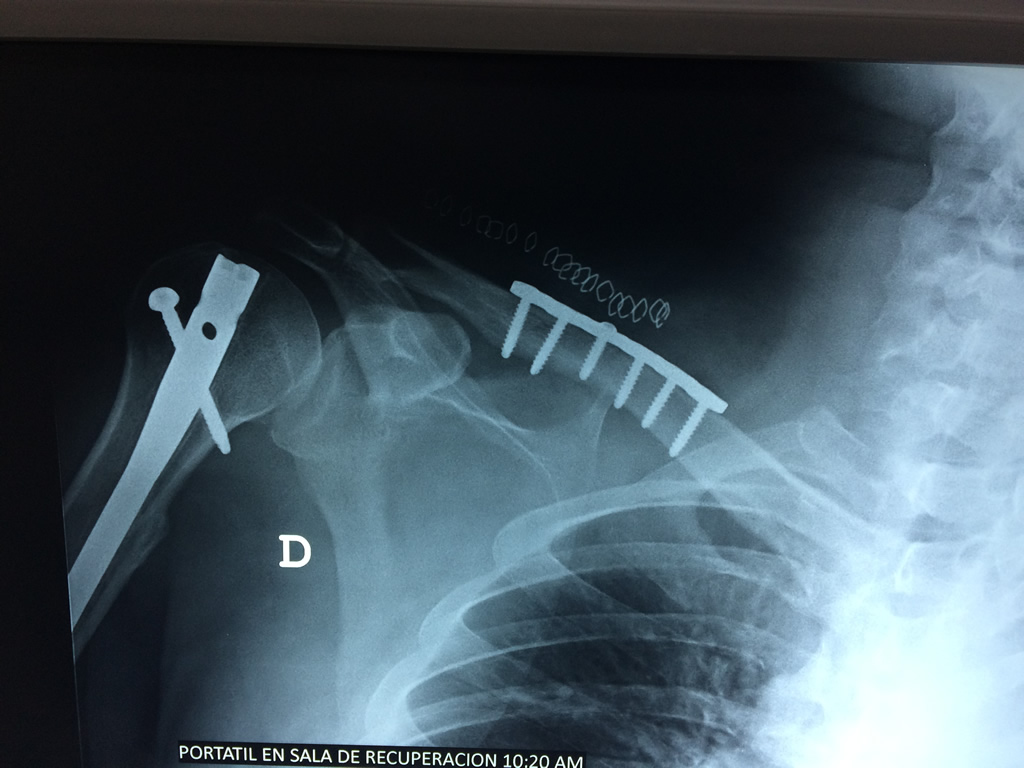

Cirugías de Húmero - Clavícula